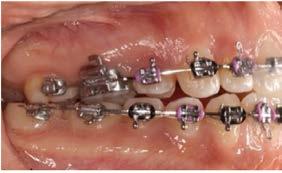

Objetivo: presentar un caso clínico de paciente con mordida abierta anterior, clase II y deglución atípica tratada con aparatología fija ortodóntica.

Caso clínico: paciente femenino de 19 años, patrón dolicofacial, perfil convexo, clase II esqueletal debido a una retrusión mandibular, mordida abierta anterior esqueletal, clase II molar, clase canina no establecida por mordida abierta, apiñamiento severo superior e inferior y deglución atípica.

Resultados: obtención de una clase canina I y clase molar II funcional, se corrigieron las sobremordidas horizontal y vertical, y se logró la coincidencia de líneas medias facial y dental. El manejo de la mordida abierta anterior se llevó a cabo por medio de la corrección del hábito de deglución atípica con la ayuda de spikes de resina, elásticos intermaxilares y arcos utility, y se obtuvieron buenos resultados estéticos, dentales y funcionales.